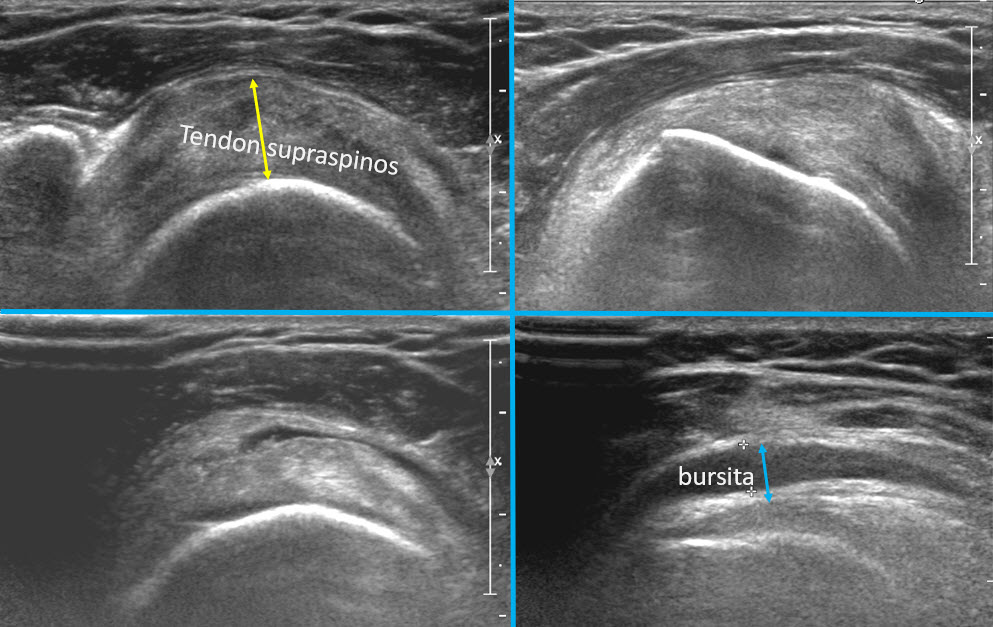

Experiența personală, susținută și de studiile privitoare la ecografia umărului, îmi permit să afirm că stația intermediară între radiografie și rezonanța magnetică este ecografia umărului.

Ecografia umărului are anumite particularități, comparativ cu alte articulații. Umărul fiind cea mai mobila articulație din corp, putem să examinăm în dinamică majoritatea structurilor umărului, fără a fi întotdeauna nevoie să folosim metode mai avansate cum este rezonanța magnetică.

Acest lucru este justificat și statistic, majoritatea patologiei umărului la pacienții fără traumatisme este dată fie de patologia coafei rotatorilor, care este vizibilă integral ecografic, fie de patologia degenerativă, care este și ea evidentă ecografic și radiografic.

Examinarea ecografică a umărului

Dupa radiografie, decizia cea mai frecventă este de a alege între ecografie și rezonanță magnetică.

Aceasta decizie se face în funcție de patologia inițială suspectată și, bineînțeles, de aspectul radiografiei. Decizia este uneori ușoară, atunci când pe examinare se vede o calcificare în spațiul subacromial, care orientează diagnosticul spre o patologie a coafei rotatorilor și prin urmare prima alegere ar fi ecografia. Dacă radiografia nu evidențiază nimic și clinica pacientului sugerează o leziune intraarticulară, rezonanța magnetică, care are posibilitatea să vizualizeze inclusiv patologia intraarticulară, este varianta mai bună.

Avantajul major al ecografiei este posibilitatea de efectua examinare în dinamică, vizualizând structurile în mișcare și permite, de asemenea, examinare focalizată exact asupra regiunii dureroase.

În cazul detecției patologiei inflamatorii intraarticulare sau intrabursale, se poate lua decizia unei intervenții minim invazive (evacuare bursita subacromială, injectare intraarticulară sau intrabursală de mix antiinflamator și analgezic) sub ghidaj ecografic.